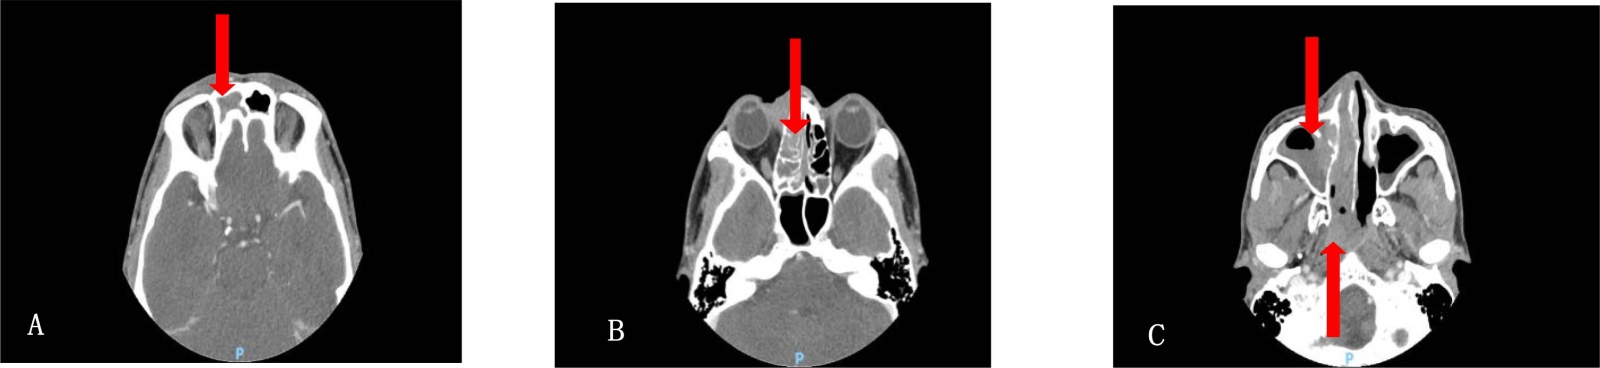

例3:患者男,71岁,2年前因“发现左侧鼻翼肿物4年”于2023年3月6日入院,鼻部无疼痛,无肿物破溃,期间该肿物逐渐增大,无鼻塞、鼻腔出血,无嗅觉减退。查体:鼻翼无扇动,左侧鼻翼见一肿物,大小约2 cm × 2 cm,表面无破溃,质软,无压痛。入院后完善三大常规及生化检查无特殊,排除手术禁忌症,遂行鼻部肿物切除术,手术过程:局麻后于肿物最高处切开,钝性分离,分离肿物周围组织并游离肿物,肿物无蒂,与周围组织分界较清,无明显粘连,沿肿物边缘安全距离(约0.5 cm)并连同肿物,完整切除,见肿物无残留,冲洗术腔后间断缝合,并放置引流管。因初步考虑肿物为良性病变,故术中未送冰冻病理检查。术后常规病理示:(左侧鼻翼肿物)小圆细胞恶性肿瘤,结合免疫组化及FISH检测结果,符合骨外尤文肉瘤,免疫组化:CD99(+),F1i-1(+),CD56 (+),CKpan少量(+),Ki-67(+,约10%),CAM5.2(部分+),Syn灶性(+),Vimentin(+),S-100(-),Desmin(-),Myogenin(-),EMA(-),CD34(-),LCA(-),SMMHC(-)。FISH检测:EWSR1基因断裂检测阳性。术后无不适,常规拆线,术区恢复可,建议患者按骨外尤文肉瘤的常规治疗方案行放化疗,但患者拒绝,嘱定期随访。现患者术后2年余,复诊行鼻部MRI示:鼻翼尤文肉瘤术后,未见明确复发征象(见图5)。目前恢复尚可。

Figure 5. Nasal MRI scan: after surgical resection of nasal ala Ewing’s sarcoma: no definite signs of recurrence

5. 鼻部MRI鼻翼尤文肉瘤术后,未见明确复发征象